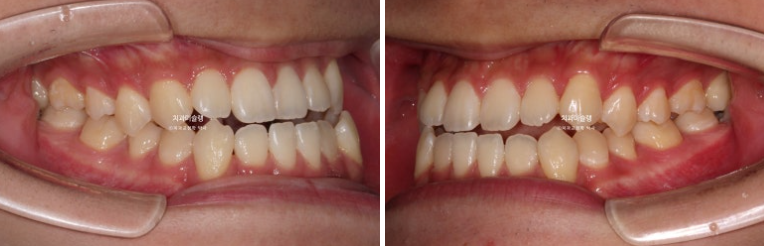

23.06

23년 교정치료를 위해 내원한 환자분입니다.

중심선이 어긋나있고 앞니 개방교합이 보입니다.

주걱턱으로 인해 앞니가 거꾸로 물리는 반대교합이 있습니다.

어금니 교합관계도 심한 3급입니다.

골격분석결과 양악수술이 필요한 상황이지만 환자분은 양악수술을 원치 않으셨습니다.